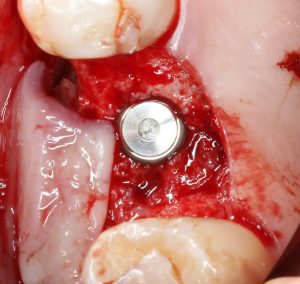

Если лунка подготовлена правильно, то имплантат проваливается в неё почти полностью:

и докручивается до правильного положения несколькими оборотами.

Еще раз акцентирую внимание на том, что Astra Tech — субгингивальная имплантационная система. А это значит, что для неё выполняются те же правила позиционирования, что и для других субгингивальных имплантационных систем. Читайте здесь>>.